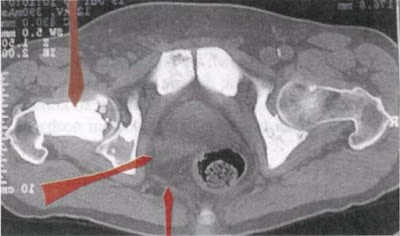

He incluido en el texto esta imagen y las siguientes porque ilustran muy bien la locura de los diagnósticos de la medicina tradicional.

Este paciente de 64 años, va a un urólogo desde hace años para hacer controles de la próstata (conflicto: divorcio, nuevo matrimonio...). A causa de estas fotografías un día el doctor se le presentó con una cara larga y le explicó que le quedaban pocas semanas de vida, que todo el vientre estaba lleno de metástasis (entiéndase la mancha blanca). El informe del radiólogo había hablado de “metástasis osteoblástica”. Con eso ya se había pronunciado la condena a muerte. Cuando el paciente vino a mí con sus lastras durante un seminario en Mallorca, le pude explicar cosas que lo alegraron mucho. Seguidamente nos reímos mucho juntos.

El lóbulo posterior, agrandado, de la próstata (flecha de abajo a la izquierda) está atravesando una tuberculosis líquida caseosa (sudor nocturno) y produce temporalmente un desplazamiento del recto de la posición central hacia la derecha.

Los puntos óseos blancos (por ej. la flecha de arriba) son ex-osteolisis recalcificadas y muestran que el paciente, que ahora está de nuevo felizmente casado, ha resuelto positivamente su conflicto de autodesvalorización (“en el vientre ya no valgo nada”). Eso no excluye que (flecha de arriba a la derecha) no pueda sufrir una nueva y pequeña osteolisis coincidiendo con una nueva recaída en las zonas recalcificadas.

De candidato a la muerte, en el giro de unos pocos minutos, volvió a ser un hombre alegre que seguía preguntándose desconcertado: “Doctor, ¿de verdad cree que todo está ahí?”.

Para estos pacientes, literalmente asustados por la muerte misma, es mucho más difícil tener la certeza de volver a estar sanos (en este caso: recién cuando termine la intensa y floreciente TBC ), solo por el hecho de creer, a pesar que nunca han estado realmente enfermos, en una muerte inevitable, que vendrá al cabo de unas pocas semanas.